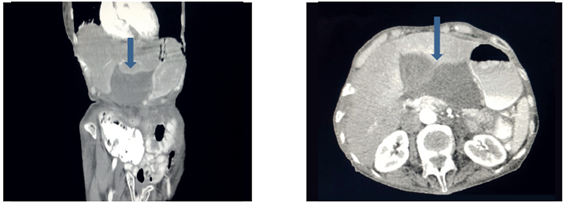

El Servicio de Medicina Interna solicitó interconsulta con Cirugía General y ordenó una tomografía computarizada de abdomen con contraste, en la cual se encontró vesícula biliar distendida, de ubicación heterotópica subhepática izquierda, sin cálculos en su interior (figuras 1 y 2).

En general, el diagnóstico prequirúrgico es casi imposible en primera instancia, de ahí que se somete a cirugía como abdomen agudo, en la que se practica laparotomía exploratoria. Solo se llega a esta si se tiene alta sospecha a partir de la historia clínica del paciente y de las ayudas imagenológicas como sucedió en estos dos casos, luego de múltiples estudios previos, distensión vesicular reportada por ecografía, ubicación heterotópica de la vesícula revelada en la TC y rotación del hilio en la colangiorresonancia magnética que orientaron hacia el diagnóstico de torsión de la vesícula biliar (figuras 1, 2, 6 y 7).